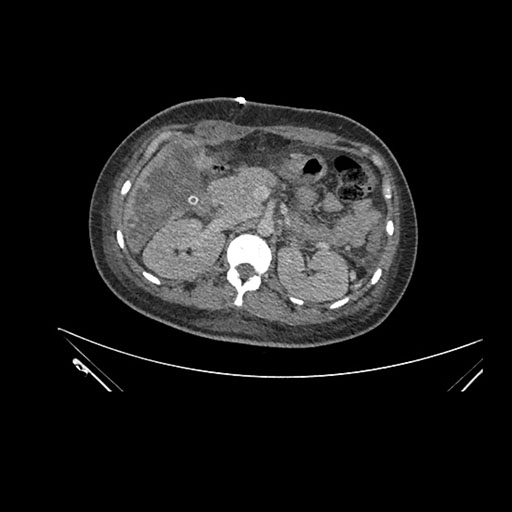

Axial Arterial

Axial Venous

Imaging analysis

Based on initial findings, which issue(s) would you be most concerned about?